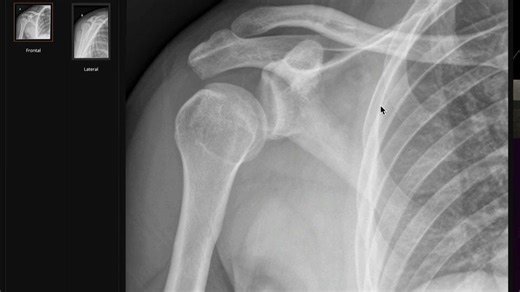

The 'Lightbulb Sign' doesn't always mean a posterior dislocation

6、肩关节后脱位影像教学〖Radiology Channel〗双语精校